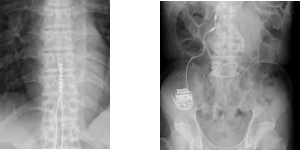

一般撮影の撮影画像

骨の画像

MRI 撮影前の禁忌事項

| 心臓ペースメーカー | 人工内耳 |

| 脳脊髄刺激電極 | 神経刺激装置 |

![]() |